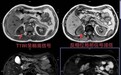

结合影像(如图1)所示,高度怀疑肾癌可能。为了进一步明确诊断,立刻安排加做增强扫描(图2—3),影像诊断结果:肾癌。知道结果的熊先生心情非常低落,他很疑惑自己在日本体检多次未见异常,为何在国内检查一次就发现问题?

答案是:针对软组织病变,有些病变密度差异不大,CT无法发现,另外超声的检查与检查者操作技术水平关系非常大,熊先生情况就是肾脏病灶与正常肾实质密度差异不大,所以CT没有显示出来,而磁共振弥补以上缺陷,有助发现肾脏早期微小病变。